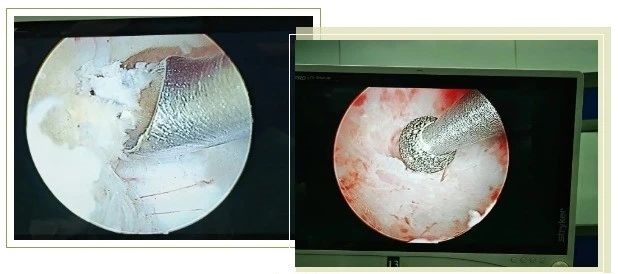

近日,在巴巴多斯伊丽莎白女王医院,一场融合现代影像技术与传统中医的创新治疗赢得了当地患者与医生的一致好评。第7批援巴巴多斯中国医疗队超声科医生敖梦与中医专家袁野,联手为一位患顽固性颈椎病的女教师Dora实施了超声引导下的针灸治疗,显著缓解了其持续8个月的颈肩放射痛。